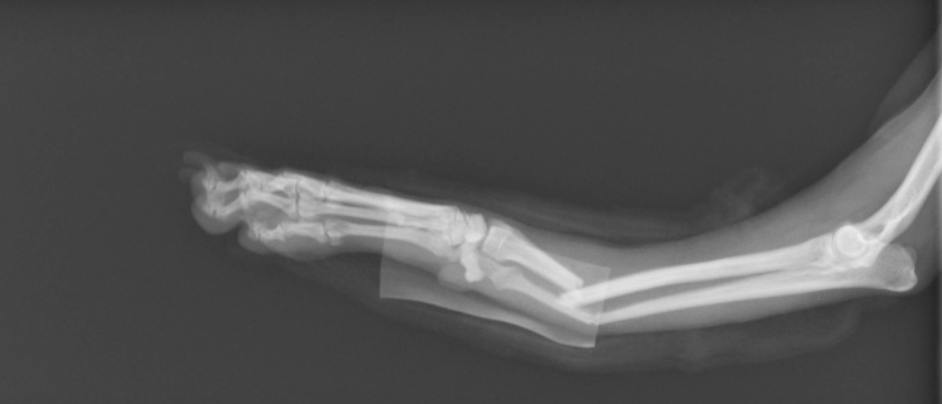

まず痛みについてです。当然犬も痛いです!しかし我慢強い子はあんまり泣き叫んだりしないこともあります。ですが、四肢の骨折では「挙上」といって足が地面に接地できなくなります。またズレがひどいと明らかに曲がらない方向に骨が曲がったりします。これは痛いですよね。

写真でも痛そうなX線の写真を出しております。この子は他の病院でバンテージと添木で治療を受けましたが、どんどんズレてしまった様です。しかし注意点として、犬の骨折に関してはバンテージのみで治ることはかなり稀です。内固定という手術をしないと骨は曲がってくっついてしまったり、結果歩くことが困難になります。骨折は若い小型犬にとても多く、万が一治療が上手くいかないと一生モノの傷になってしまうのです。